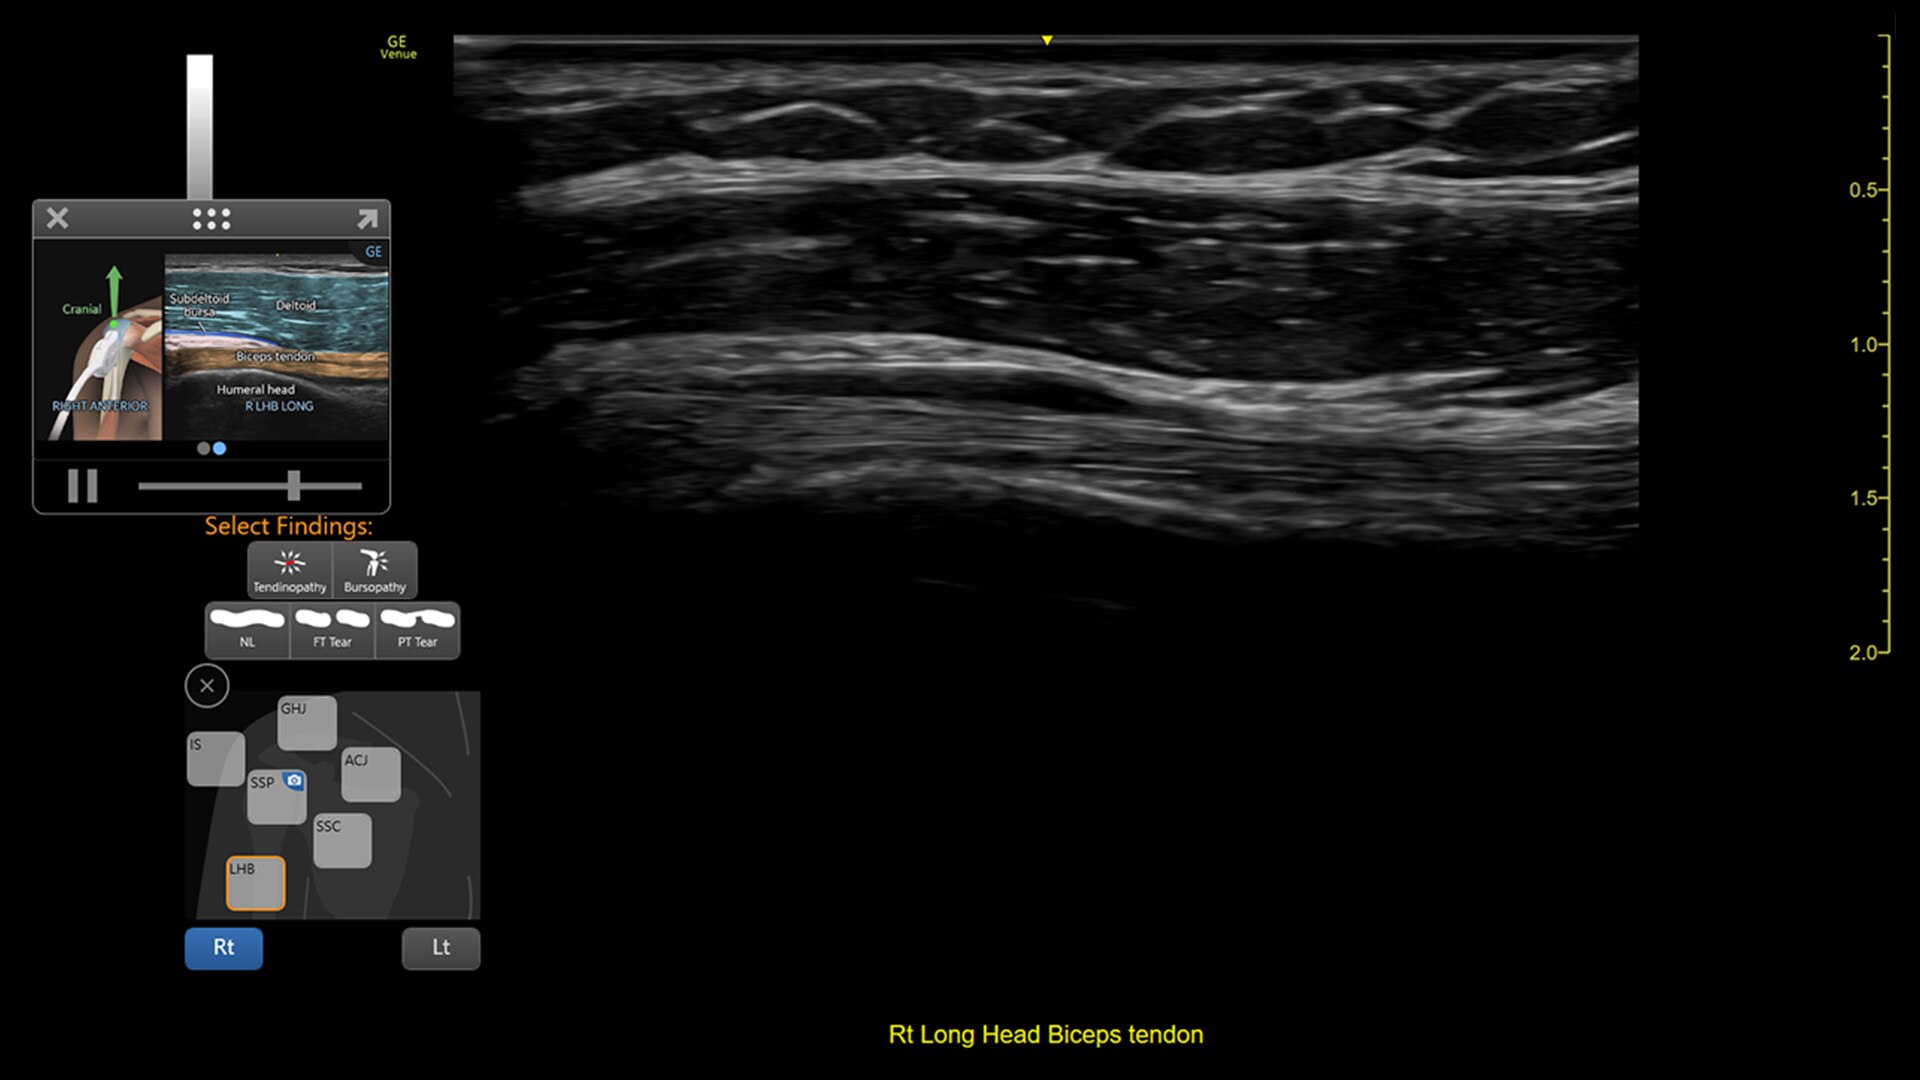

VENUE COACH MSK

Simplifying MSK scans

This easy-to-use exam documentation tool assists users through exams by providing reference images and anatomy markups. Multiple anatomical areas and helpful video tutorials help clinicians to acquire the scans they need.

• MSK Diagrams: Simplifies documentation and assists the clinician in follow up for patients. No need to manually type findings—you can simply assign a label from a pre-populated list that correlates with the images. Get a single view diagram with one click image storing, keep track of assessments and show trends in response to therapy.

• Reference Image: Reference image provides anatomy mark-ups to assist novice users in scanning the correct anatomy

• Bilateral mode: Helps you to view the opposite side of the same zone for comparison (available for Shoulder preset)